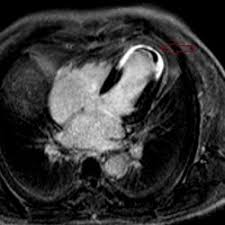

Mrt Klart Akuten Brustschmerz

Mrt Klart Akuten Brustschmerz from www.aerztezeitung.de